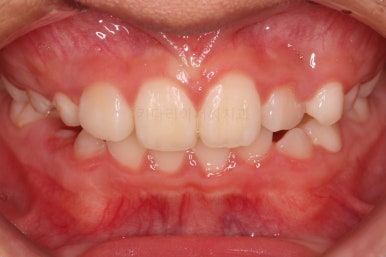

우선 처음 내원 하셨을 때의 입안의 상태를 보겠습니다.

아직 나이가 어리다 보니 곳곳에 유치가 남아 있었어요. 보통 이렇게 영구치가 다 나오지 않았을 경우, 보호자분들은 "치아교정"에 대해서는 전혀 생각해 보시지 않으셨을 수 있어요.

이번 환자분의 경우도 앞니가 거꾸로 물리는 상황이어서 치료가 필요한 상황이였습니다.